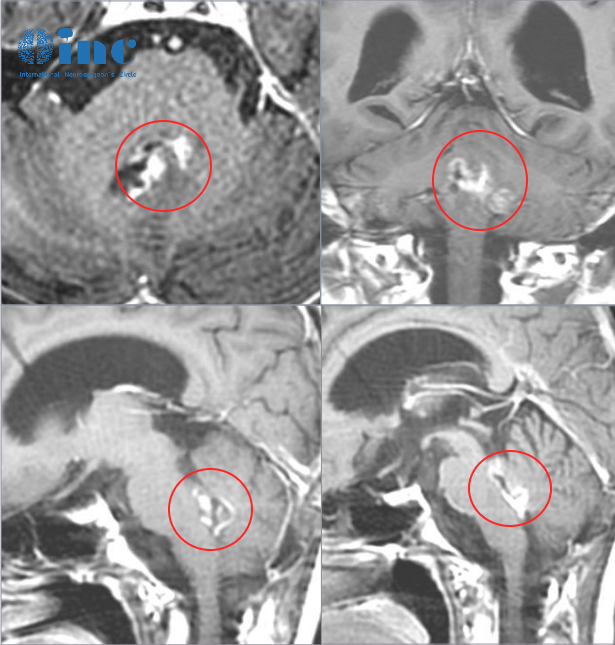

- 文章標題:四腦室膠質瘤:“手術治療是必要的,等待可能會給腫瘤繼續(xù)生長的機會!”